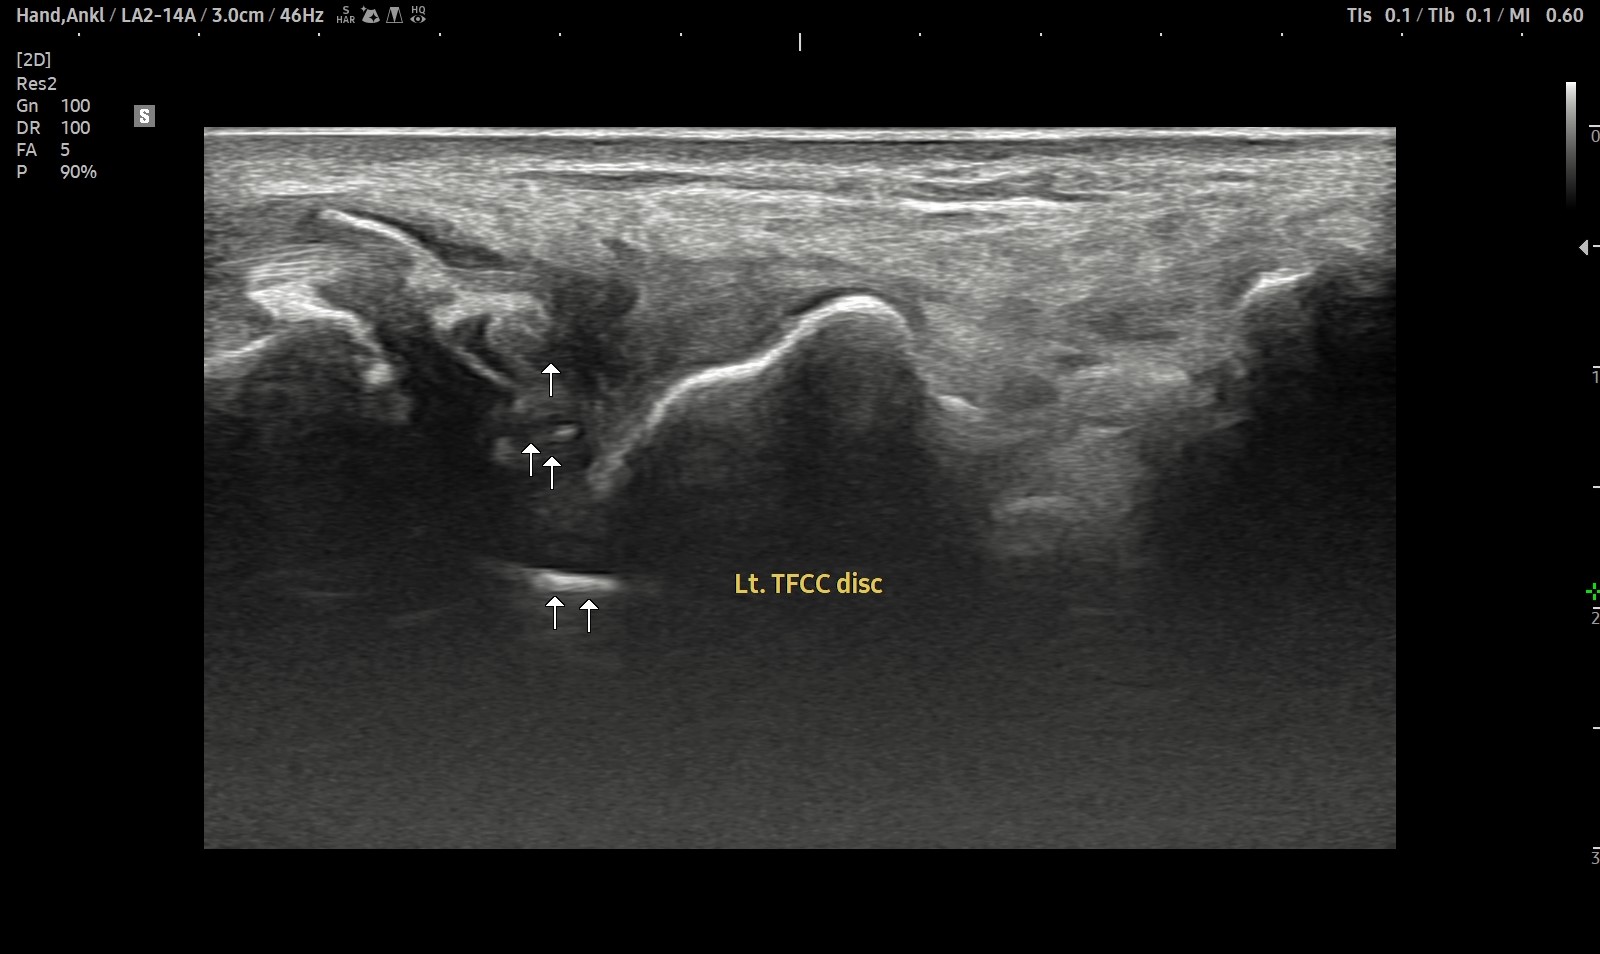

- 치료기간 : 25 . 5 . 7 ~ 25 . 8 .12

- 치료횟수 : 4cycle(20) 회

치료전

치료후